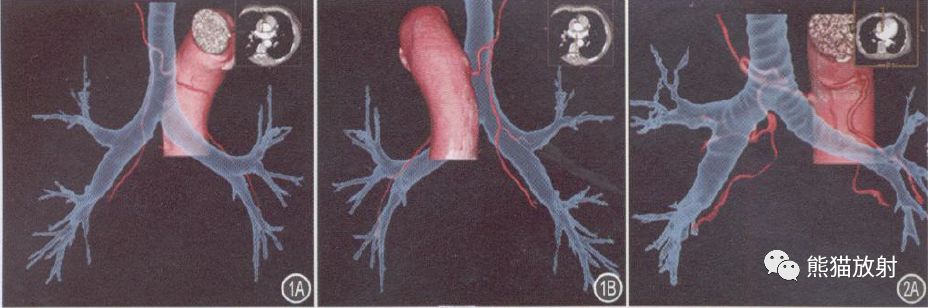

图4A~ C 右肺癌, BA呈R2L1, R1 源自右锁骨下动脉, R2 源自降主动脉前,R1 、R2 均增粗、迂曲, 走行至病灶内, 供血肺癌;L1 起源于降主动脉前壁, 起始处较扭曲, 并分为2支, 均沿左主支气管上壁走行, 分布至左肺上、下叶。

图5A~ C 左肺支气管扩张, 轴位肺窗显示病灶, VR示来源于肝固有动脉的血管分支与BA相互交通吻合形成广泛血管网络, 供血同一病灶, 其中左侧1支BA异位起源于左锁骨下动脉。